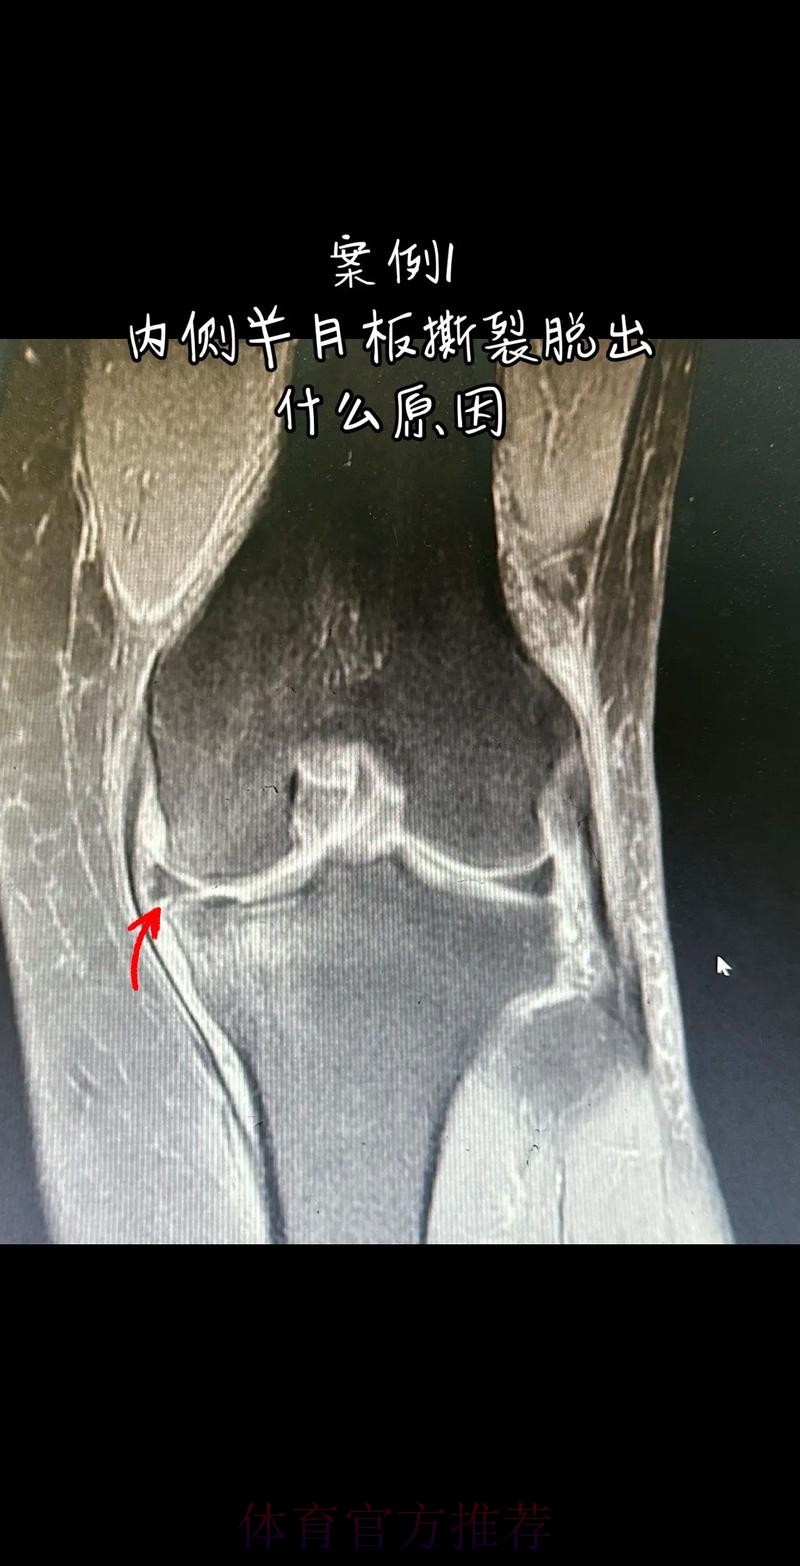

这条“官方 阿拉巴左膝内侧半月板撕裂 预计伤缺6-8周”的声明一出 不只是伤病通告那么简单 它背后牵动的是皇马后防体系的重塑 奥地利国家队备战计划的调整 以及一名顶级后卫职业生涯中一次关键的健...